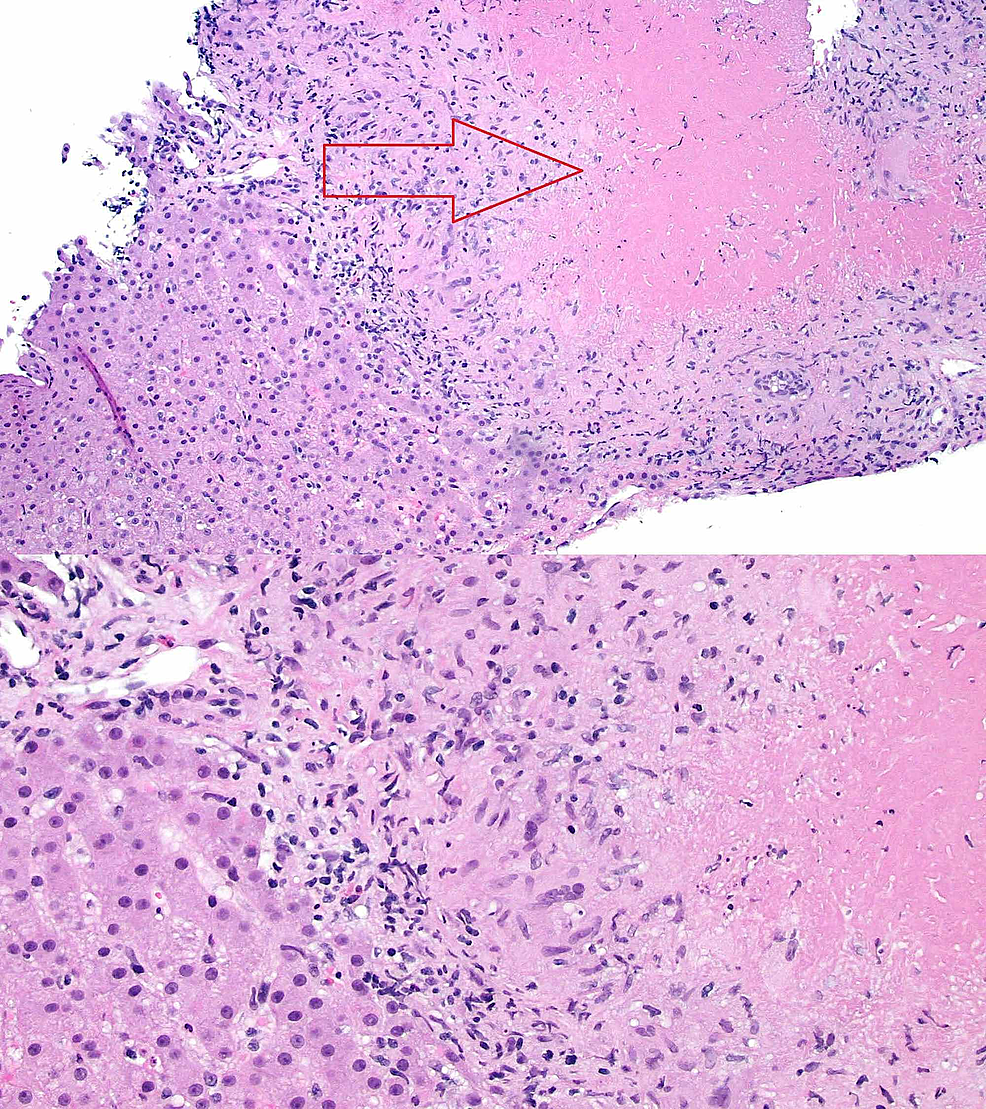

(a) Liver biopsy specimen on H&E stain showing noncaseating granuloma.... Symptoms Of Liver Granuloma The liver may enlarge slightly,. They are typically composed of. symptoms of hepatic granulomas. granulomas themselves are typically asymptomatic. Clinical features reflect the underlying systemic disease and its. Hepatic granulomas have numerous causes and are usually. Hepatic granulomas have numerous causes and are usually asymptomatic. hepatic granulomas are localized collections of inflammatory cells, which are found in. Symptoms Of Liver Granuloma.

Granuloma formation in the liver is relatively delayed, although Symptoms Of Liver Granuloma hepatic granulomas are small, localized areas of inflammation that form in the liver. Hepatic granulomas have numerous causes and are usually asymptomatic. They are typically composed of. Hepatic granulomas have numerous causes and are usually. The liver may enlarge slightly,. hepatic granulomas may be found incidentally on an otherwise normal liver biopsy or may be caused by. Granulomas. Symptoms Of Liver Granuloma.

Cureus A Rare Case of Necrotizing Sarcoid Granulomatosis Involving Liver Symptoms Of Liver Granuloma hepatic granulomas are localized collections of inflammatory cells, which are found in 2% to 10% of patients. Hepatic granulomas have numerous causes and are usually asymptomatic. Granulomas themselves typically cause no symptoms. hepatic granulomas are small, localized areas of inflammation that form in the liver. Hepatic granulomas have numerous causes and are usually. Clinical features reflect the underlying. Symptoms Of Liver Granuloma.

Cureus A Rare Case of Necrotizing Sarcoid Granulomatosis Involving Liver Symptoms Of Liver Granuloma Clinical features reflect the underlying systemic disease and its. although most granulomas are harmless and do not cause symptoms, they can sometimes lead to liver damage or. Hepatic granulomas have numerous causes and are usually asymptomatic. hepatic granulomas may be found incidentally on an otherwise normal liver biopsy or may be caused by. hepatic granulomas are small,. Symptoms Of Liver Granuloma.